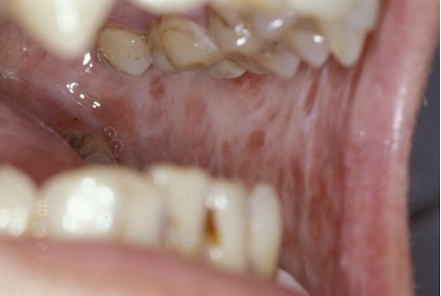

1、口腔粘膜下纤维性变(OSF)

口腔粘膜下纤维性变是一种慢性进行性疾病,与咀嚼槟榔等因素有关。在湖南及咀嚼槟榔地区发病率较高。是一种癌前状态,部分患者合并有口腔癌。主要表现为口腔黏膜灼痛、口干等自觉症状,及进行性张口受限、吞咽困难。

我科对口腔粘膜下纤维性变有丰富的治疗经验,对缓解粘膜灼痛及张口受限的治疗方法,收到了良好的疗效。已开展治疗如:去除致病因素、物理治疗、局部药物治疗、中西医结合治疗、手术治疗等。